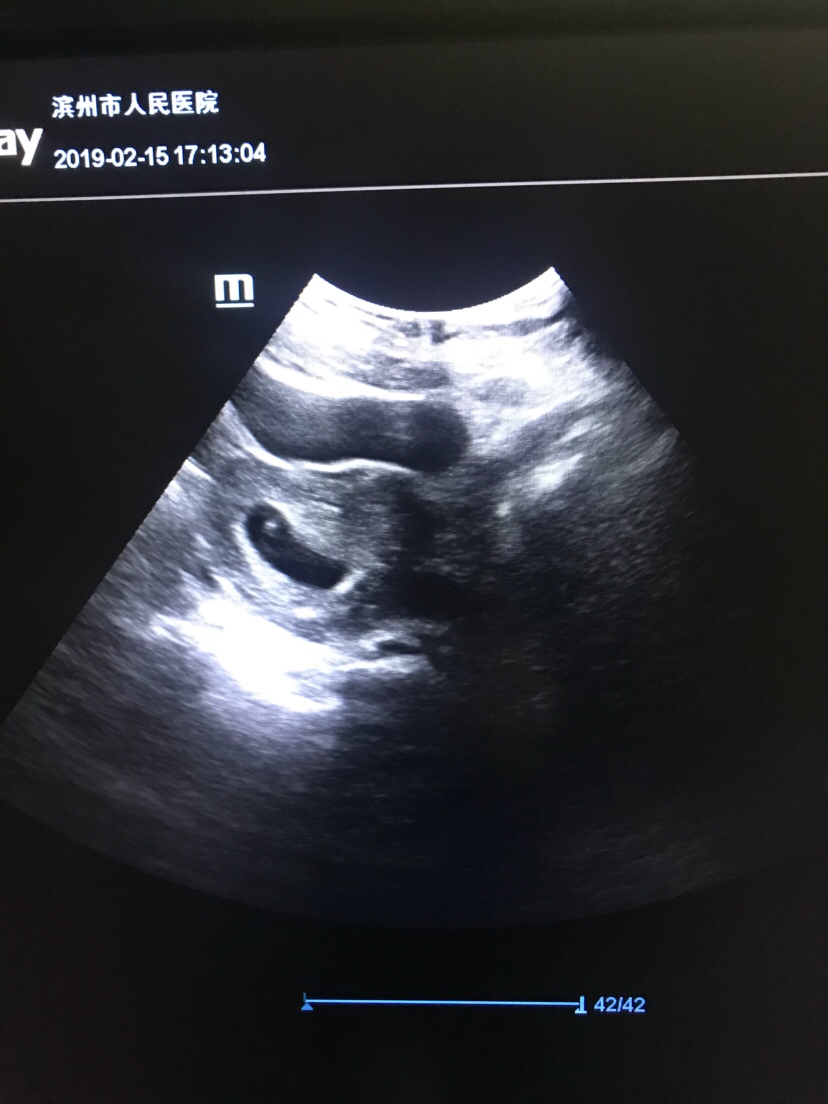

HYGJCQ70[帖主]:六周两天

我今天去照都有了 但是有宫腔积液 医生还开了保胎药 吓死了